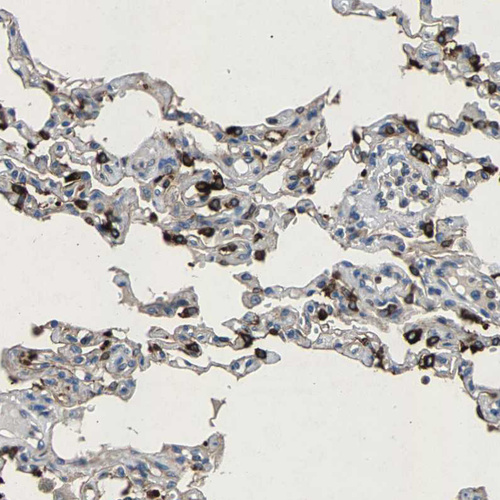

Immunohistochemistry analysis in human lung and liver tissues using HPA022268 antibody. Corresponding LPCAT1 RNA-seq data are presented for the same tissues.